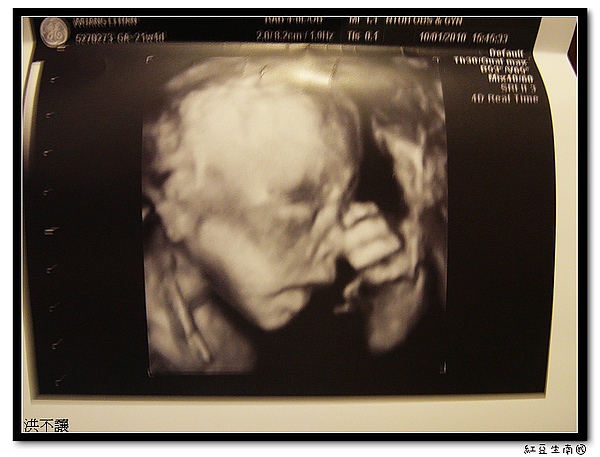

高層次檢查-21週

21週的產檢做了高層次,要到台大的兒醫大樓的9樓去做,醫生還滿細心的,仔細檢查頭部、唇、四肢和心臟,而且還換第二個醫生做DOUBLE CLECK,可是第二個醫生不知是排班排不好還安怎,口氣和心情都不佳,讓我有點想投訴~~

不過,看到寶貝TWO都很健康,我和老爺都很高興,隨即轉往門診去看肚子是否還是宮縮.沒想到醫生一摸、眉頭一皺,說再去兒醫大樓測宮縮,還是太硬了,如果不過就要立即住院,我整個心往下沉,接下來醫生說什麼都聽不到了,由老爺代回答.

心情沉重地去測宮縮,躺了一個多小時,還好不是很頻繁,暫時回家安,但不可以做事和出門走動,要乖乖躺在床了,唉~~寶貝TWO我們一起加油奈!